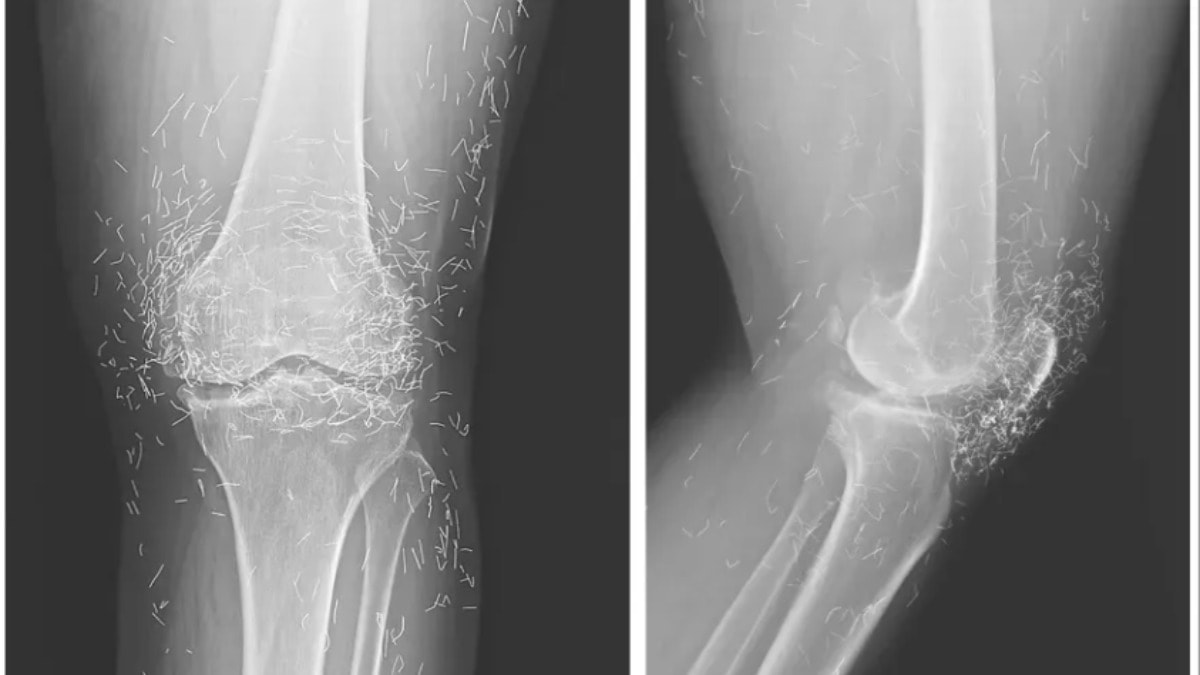

Hastanede yapılan tetkikler sonucunda, röntgendeki altın ipliklerin, kadının düzenli olarak uygulattığı altın iplik akupunkturu seanslarında bilerek bırakıldığı öğrenildi. Bu uygulamada steril kısa altın iplikler dokuya yerleştirilerek sürekli uyarım sağlanması amaçlanıyor.

Doktorlar, ipliklerin vücutta bırakıldığını ancak önceki vakalara dayanarak bunun bazı riskler taşıyabileceğini belirtti. Daha önce benzer tedavi gören hastalarda kist oluşumu gözlemlenmişti. Ayrıca ipliklerin zamanla yer değiştirme riski bulunuyor.

Ayrıca bu ipliklerin görüntüleme teknikleri üzerinde de olumsuz etkileri olabiliyor. Röntgenlerde yorumlamayı zorlaştırmasının yanı sıra, manyetik rezonans (MR) görüntülemelerinde ipliklerin hareket etmesi ve damarlara zarar vermesi riski bulunduğu vurgulandı.

Doktorlar, bu tür geleneksel tedavi yöntemlerine başvuran hastalarda altın ipliklerin varlığının mutlaka göz önünde bulundurulması gerektiğini belirtiyor. Neyse ki ipliklerin röntgende rahatça görülebilmesi sayesinde konumları zamanla takip edilebiliyor.